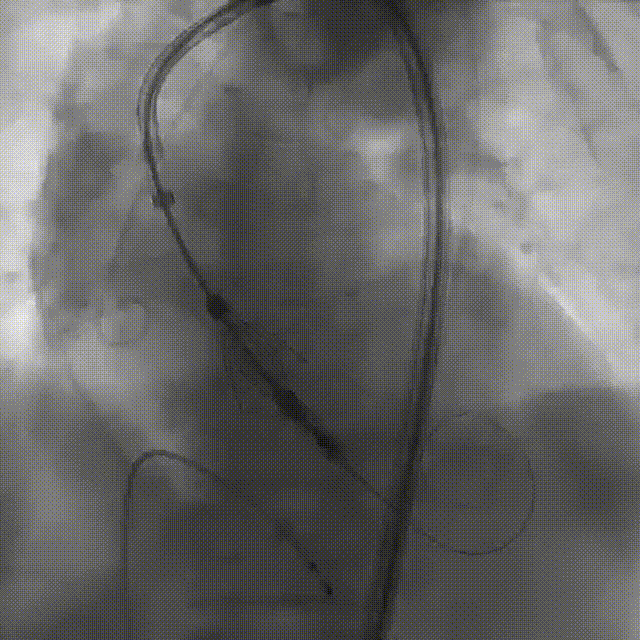

2026年伊始,TaurusTrio经导管主动脉瓣系统在武汉大学人民医院,中国科学技术大学附属第一医院,安徽医科大学第一附属医院,安徽医科大学第一附属医院北区,首都医科大学附属北京安贞医院南充医院,海南省人民医院等多家临床中心成功开展上市后全国首批植入。这不仅是TaurusTrio正式走向广泛临床应用的重要里程碑,更标志着中国单纯主动脉瓣反流介入治疗正式迈入了“心键合璧”的全新纪元。